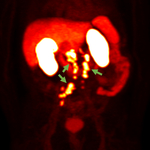

MONROE TOWNSHIP, N.J. & OXFORD, England–(BUSINESS WIRE)–Blue Earth Diagnostics, a Bracco company and recognized leader in the development and commercialization of innovative PET radiopharmaceuticals, today announced results from its Phase 3 SPOTLIGHT trial that evaluated the impact of various clinical factors, including baseline Prostate Specific Antigen (PSA) levels, PSA doubling time and Gleason score, on detection rates (DRs) for 18F-rhPSMA-7.3 in recurrent prostate cancer. 18F-rhPSMA-7.3 is an investigational high affinity radiohybrid (rh) Prostate-Specific Membrane Antigen-targeted PET imaging agent. The results were reported in an oral presentation at the American Society for Radiation Oncology (ASTRO) 2022 Annual Meeting in San Antonio, Texas.

The findings presented at ASTRO included analyses of clinical factors impacting DRs for 18F-rhPSMA-7.3 evaluated by three blinded central readers: DRs, including region-level analyses, stratified by baseline PSA levels, PSA doubling time, Gleason score and prior treatment (radical prostatectomy with or without radiotherapy, or radiotherapy only). For example, results showed that among the 389 patients in the Evaluable PET Scan Population, the patient-level DR of 18F-rhPSMA-7.3 PET by majority read was 83% (322/389). When stratified by PSA level, the DRs were: PSA <0.5 ng/mL: 64% (77/121); PSA ≥0.5 and <1 ng/mL: 76% (51/67); PSA ≥1 and <2 ng/mL: 93% (42/45); PSA ≥2 and <5 ng/mL: 98% (86/88); PSA ≥5 and <10 ng/mL: 94% (34/36); and PSA ≥10 ng/mL: 100% (32/32). As noted previously, no serious adverse reactions were attributed to 18F-rhPSMA-7.3 PET in the SPOTLIGHT study. Overall, 16 (4.1%) patients had at least one treatment-emergent adverse event that was considered possibly related/related to 18F-rhPSMA-7.3. The most frequently reported events were: hypertension: 1.8% (n=7); diarrhea: 1.0% (n=4); injection site reaction: 0.5% (n=2), and headache: 0.5% (n=2).

rhPSMA compounds consist of a radiohybrid (“rh”) Prostate-Specific Membrane Antigen-targeted receptor ligand which attaches to and is internalized by prostate cancer cells and they may be radiolabeled with 18F for PET imaging, or with isotopes such as 177Lu or 225Ac for therapeutic use – creating a true theranostic technology. They may play an important role in patient management in the future, and offer the potential for precision medicine for men with prostate cancer. Radiohybrid technology and rhPSMA originated from the Technical University of Munich, Germany. Blue Earth Diagnostics acquired exclusive, worldwide rights to rhPSMA diagnostic imaging technology from Scintomics GmbH in 2018, and therapeutic rights in 2020, and has sublicensed the therapeutic application to its sister company Blue Earth Therapeutics. Blue Earth Diagnostics has completed two Phase 3 clinical studies evaluating the safety and diagnostic performance of 18F-rhPSMA-7.3 PET imaging in prostate cancer: (“SPOTLIGHT,” NCT04186845), in men with recurrent disease and (“LIGHTHOUSE,” NCT04186819), in men with newly diagnosed prostate cancer. Currently, rhPSMA compounds are investigational and have not received regulatory approval.